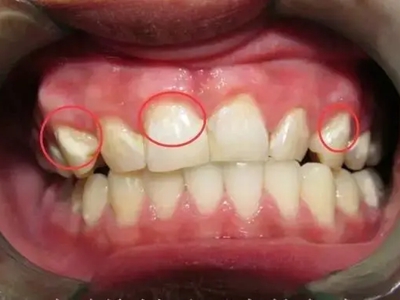

牙釉质发育不全牙齿白斑图

牙釉质发育不全患者可以仅仅出现牙齿色泽和透明度的改变,形成白垩色釉质,即类似于牙齿上有白斑,此时牙冠形态通常较完整。

牙齿

白斑

牙釉质发育不全牙齿上出现白色的斑块图

牙釉质发育不全患者牙釉质表面出现白垩色釉质,表现为牙齿表面色泽不均匀,一般无自觉症状,并且此时牙冠形态较为完整,顶端出现小的缺损。